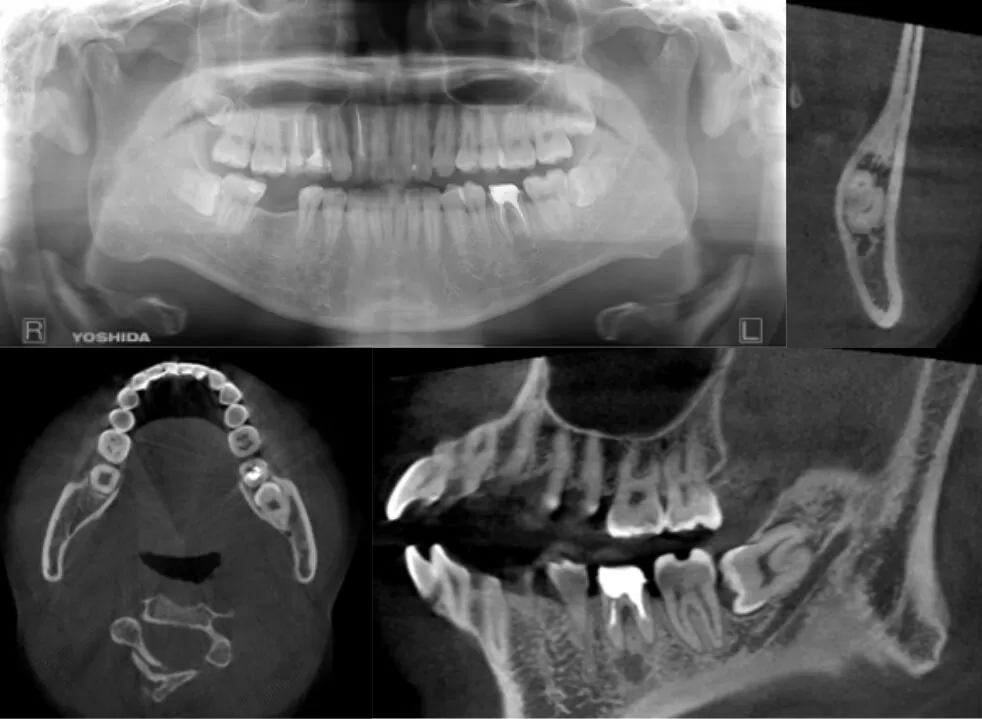

東京・大森の親知らず専門外来「おおもり北口歯科 大森院」では、歯科用CTを用いた三次元的診断を実施しています。従来のレントゲン(2D)では見えにくい情報も、CTにより骨の厚み・神経や血管の位置関係などを立体的に把握できます。

2D画像では簡単に見えるケースであっても、CTで確認すると非常に難易度の高い親知らずであることが判明することもあります。逆に難易度が低いと判定されれば、短時間かつ安全に処置を行うことも可能です。

歯科用CTを使用することで、親知らずと下顎の骨の位置関係や神経の走行をより詳細に確認することができます。これにより、神経損傷などのリスクを可能な限り低減した治療計画を立てることが可能となります。

治療前には、CTやパノラマレントゲンを使用して親知らずの位置や傾き、神経との距離を正確に評価します。

特に水平埋伏歯の場合は、「グレゴリーの分類」に基づき、9段階の難易度に分類して、適切な治療方法を導き出します。